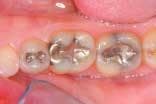

The upper and lower occlusal shots, as well as the four individual quadrants, are captured next. The four individual quadrant shots are the most powerful of the series. These are the shots where a patient can see old restorations, wear facets, recurrent decay, poor contour, etc. It is with the quadrant shot that the patient asks for dentistry. The doctor does not need to sell it!